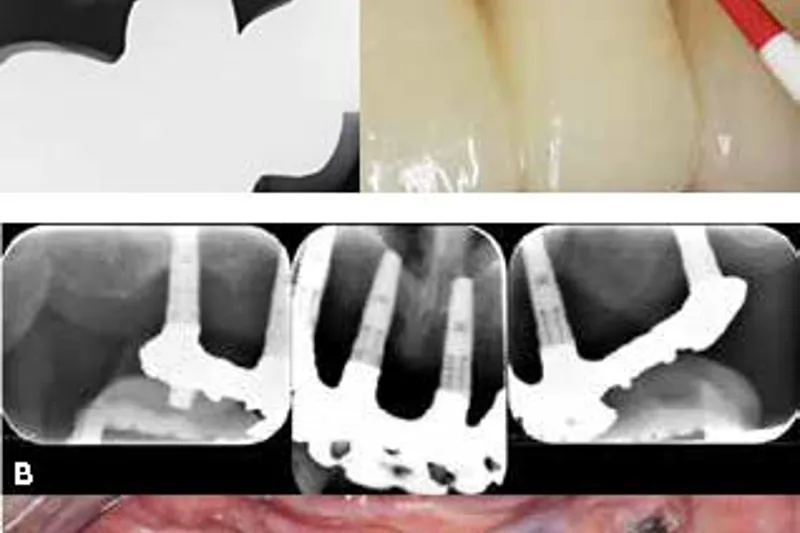

Denne oversigtsartikel sætter fokus på de vigtigste karakteristika ved periimplantær sundhed, periimplantær mucositis og periimplantitis.

Endvidere gives information om, hvordan man kan implementere den nye klassifikation i klinikken, og hvordan man stiller de rigtige diagnoser med og uden adgang til tidligere journaloptegnelser.

Til slut diskuteres validiteten af pochemåling omkring implantater, og der gives en opdatering af prævalenser og risikofaktorer for forskellige periimplantære sygdomme.